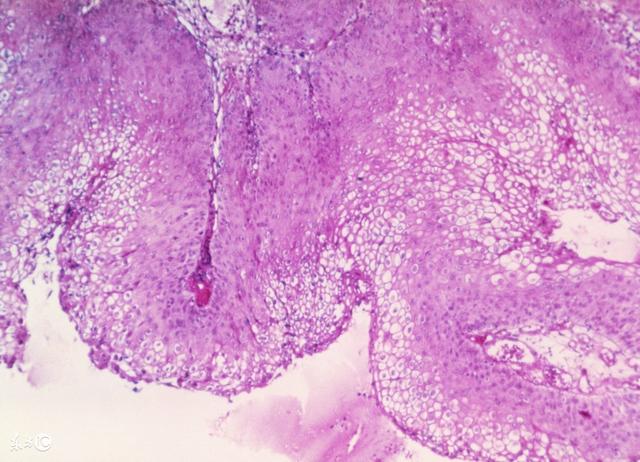

尖锐湿疣又称生殖器疣或性病疣,是一种由人类乳头瘤病毒惹起的性传布疾病。在不洁性生活后,发现生殖器部位出现赘生物,形态如菜花状、鸡冠状、丘疹状、乳头状,无痛痒感,渐渐增大增多,有些表面污秽,呈血色,易出血……假设你有这样的症状,应当高度警惕尖利湿疣。

1、菜花型

女性阴道尖锐湿疣是多见的菜花状,也是相对多见的类型,专家详细介绍:病灶明显崛起,基底较宽或有细蒂,表面布满毛刺或珊瑚样崛起,涂3%醋酸后表面构造水肿变白如雪塑状。白色布景上可见散在成团的绒球状血管。

2、地毯类型

尖锐湿疣类型还包含地毯型的症状,女性出现此病后,症状会呈现白色片状的环境,并且,普通环境下,略高出于正常皮肤、粘膜,涂3%醋酸后部分变白,表面散在呈花坛状排列的点状血管或螺旋状血管,是典范的反镶嵌阴道镜图像。

3、指状型

女性阴道尖锐湿疣还包含指状型,也被称为棒状型,这也是病变的早期表现,专家提示:病变部位涂3%醋酸后,阴道镜观察可见许多指状崛起,崛起物基质呈透明黄色,每个指状崛起内都可见到很清楚的血管袢。